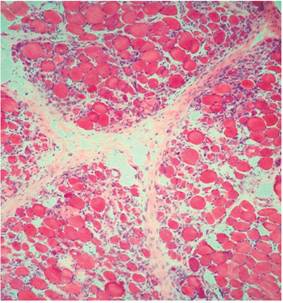

Biopsia de piel y músculo (Figuras 4 y 5): infiltrado perivascular de linfocitos en el plexo profundo, inflamación a predominio linfocítico de vasos del perimisio y atrofia perifascicular.

Existen otros síntomas y signos que pueden presentarse, como neumonitis intersticial, afectación cardíaca y disfagia, como se observó en esta paciente. Las alteraciones enzimáticas propias de la DM plantean diagnósticos diferenciales como enfermedades malignas, hepatopatías e infarto del miocardio. La DM en asociación con procesos malignos constituye un síndrome paraneoplásico. Algunos autores 5 señalan la incidencia entre un 13 %-15 % y otros 6 entre el 20 %-30 %. Los datos ofrecidos por la biopsia de piel y músculo muestran una inflamación perimisial y perivascular, y puede ocurrir atrofia perifascicular, lo que ofrece el diagnóstico.